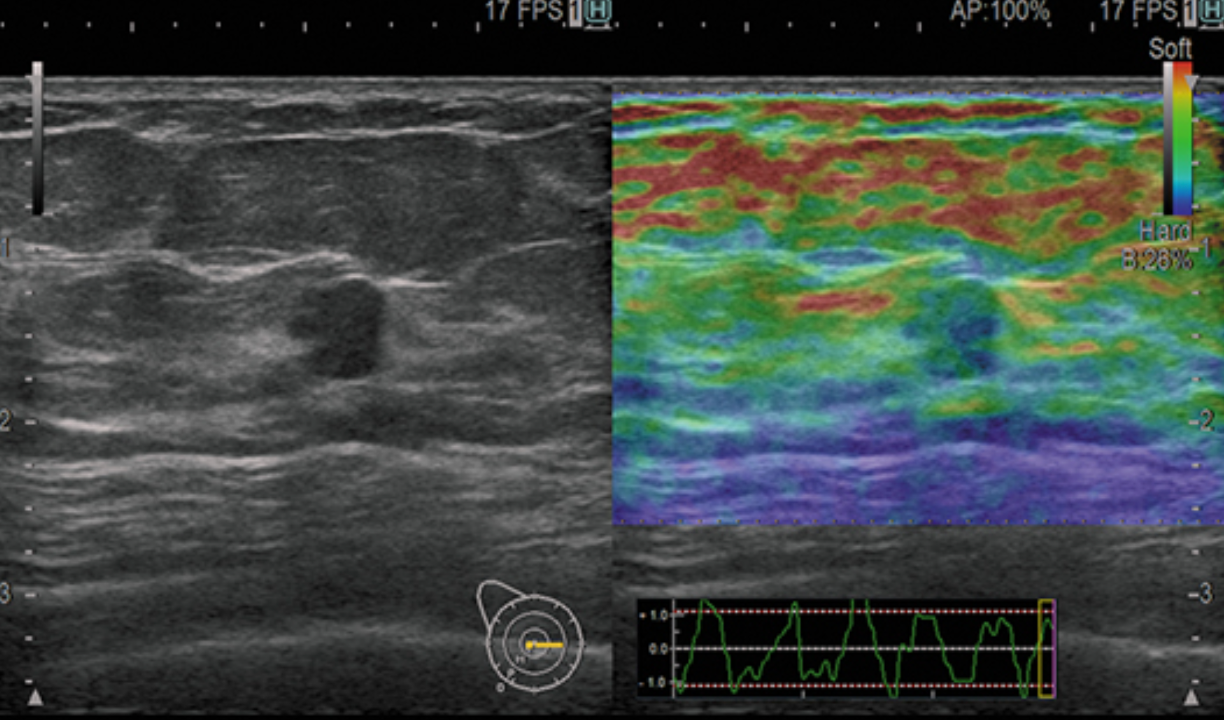

Da jeder Eingriff in den menschlichen Körper ein Blutungs- und Infektionsrisiko birgt, suchte man seit langem nach einer alternativen Methode, um die Steifigkeit der Leber zu bestimmen. Die Scherwellen-Elastographie (SWE) ist ein Ultraschallverfahren, das es erlaubt, das Ausmaß einer Leberschädigung zuverlässig auf nicht invasive Weise abzuschätzen. Es dient der Diagnose und Verlaufskontrolle bei Lebervernarbungen (Fibrose) bzw. Leberschrumpfung (Zirrhose).

Bei der Untersuchung wird die Leberelastizität als Maß für die Verformbarkeit des Lebergewebes bestimmt. Je fester und unelastischer das Lebergewebe ist, desto schneller laufen die Ultraschallwellen hindurch und verformen das Gewebe. Auf diese Weise kann der Bindegewebsumbau der Leber in hoher Übereinstimmung mit der ansonsten invasiv durchzuführenden Leberbiopsie dargestellt werden. Das Verfahren eignet sich, um den Erfolg einer medikamentösen Therapie im Verlauf zu dokumentieren.

Durch die Integration der beiden nicht-invasiven Methoden zur Beurteilung von Lebergewebe Steifigkeit (RTE und SWM), ist eine chronologische Beurteilung möglich um das Fortschreiten von Leberentzündungen und -fibrosen mit größerer Genauigkeit zu beurteilen als bisher.